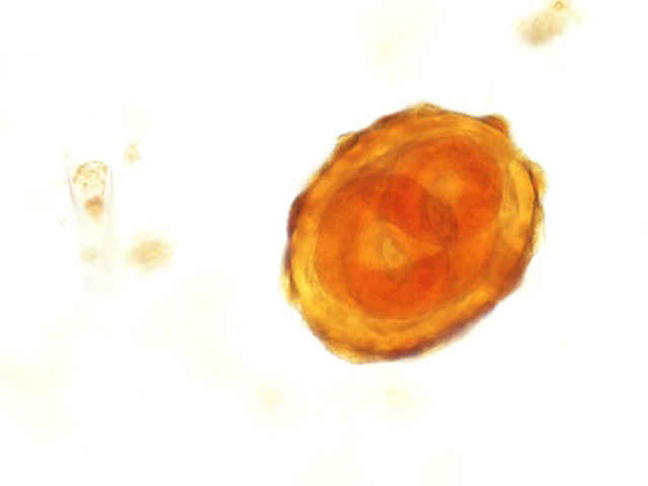

- 40x

Ascaris

Notice this is an unfertilized ova it has no corticated edges